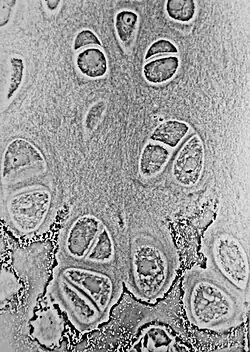

![]() Light micrograph of an undecalcified epiphyseal plate that is displaying the hypertrophic zone with its typical chondrocytes, matrix and three zones: maturation (top), degenerative (middle) and provisional calcification (bottom). | |

Histology

The growth plate has a very specific morphology in having a zonal arrangement as follows:[8]

| Epiphyseal plate zone (from epiphysis to diaphysis) | Description |

|---|---|

| Zone of reserve | Quiescent chondrocytes are found at the epiphyseal end |

| Zone of proliferation | Chondrocytes undergo rapid mitosis under influence of growth hormone |

| Zone of maturation and hypertrophy | Chondrocytes stop mitosis, and begin to hypertrophy by accumulating glycogen, lipids, and alkaline phosphatase |

| Zone of calcification | Chondrocytes undergo apoptosis. Cartilagenous matrix begins to calcify. |

| Zone of ossification | Osteoclasts and osteoblasts from the diaphyseal side break down the calcified cartilage and replace with mineralized bone tissue. |